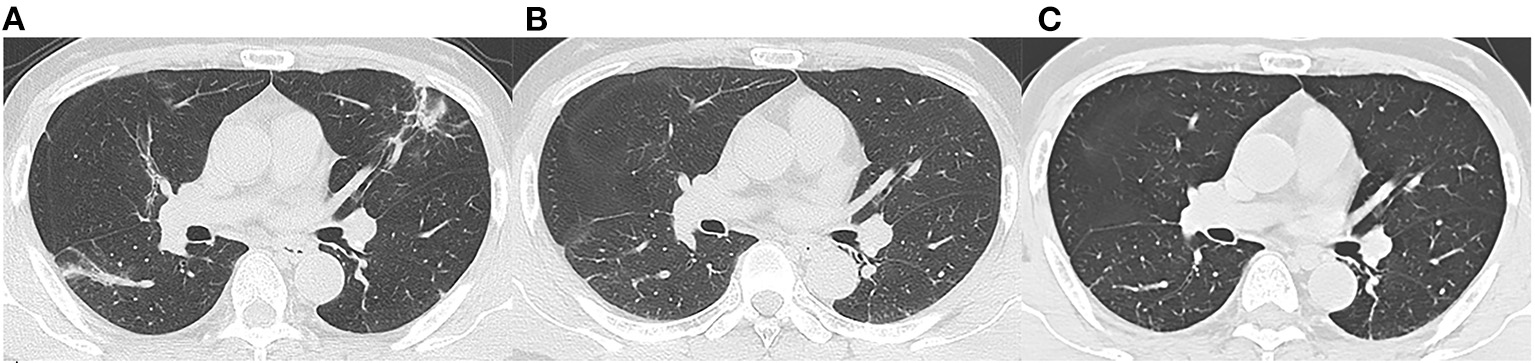

Figure 2

Follow-up chest CT images of a 52-year-old male with COVID-19. (A) At discharge, CT imaging shows parenchymal bands, irregular interfaces, and traction bronchiectasis in left upper lobe and right lower lobe. The lesions are almost revolved on the 3-month follow-up (B) and 7-month follow-up (C) CT. This patient was enrolled in non-fibrosis group.

We reviewed three CT scans for each patient. The average interval between discharge and latest follow-up was 219 days, and the average intervals of the two subgroups did not differ statistically (p = 0.066). The dynamic changes of chest CT features were listed in Table 2. As shown in Table 2, the predominant chest CT features observed at discharge included parenchymal band (73%), GGO (71%), interlobular septal thickening (68%), consolidation (46%), and irregular interface (46%). The less common CT features included reticular pattern (39%) and traction bronchiectasis (29%). The rare CT features were air bronchogram (7%) and crazy paving pattern (5%). Quantitative CT parameters calculated by the artificial intelligence software revealed that the median opacity score was 4.0 (IQR 2.0–5.0), the median volume of opacity was 178.0 ml (IQR 41.4–422.0 ml), and the median percentage of opacity was 4.3% (IQR 1.0%−12.4%). After discharge, all the quantitative CT parameters gradually decreased with time. The median opacity score, volume of opacity, and percentage of opacity on the latest follow-up CT (7 months after discharge) were decreased to 0.0 (IQR 0.0–1.0), 0.9 (IQR 0.0–12.8) ml, and 0.0% (IQR 0.0–0.3%), respectively. Twenty-five patients (61%) achieved complete radiological resolution on the 7-month follow-up CT. GGO (12%) and consolidation (10%) were almost resolved on the 7-month follow-up CT, while evidence of fibrosis, such as parenchymal band (41%), interlobular septal thickening (32%), reticular pattern (12%), and traction bronchiectasis (29%), were still obvious (Figures 2, 3).

However, the CT manifestations of pulmonary fibrosis (interlobular septal thickening, irregular interface, parenchymal band, and traction bronchiectasis) were still apparent on the 7-month follow-up CT. As reported, pulmonary fibrosis may develop in the early stage in discharged patients with SARS (11), and the fibrosis may be long-persistent (15), whereas the pulmonary fibrosis in discharged COVID-19 patients may be absorbed with time (6), which was consistent with our study (Figure 2). The reversibility of fibrosis probably indicated that the pulmonary fibrosis on chest CT did not signify actual pathologic fibrosis (14), and thus whether these lesions would completely disappear required further observation.